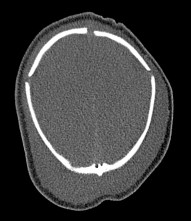

le scanner n’est pas toujours nécessaire, l’indication dépend de l’importance du traumatisme, ou au contraire devant l’absence de traumatisme rapporté chez un enfant ne marchant pas, pour rechercher un traumatisme non accidentel.

un céphalhématome bilatéral témoigne de l’absence de la suture sagittale, et est donc pathognomonique de la scaphocéphalie.